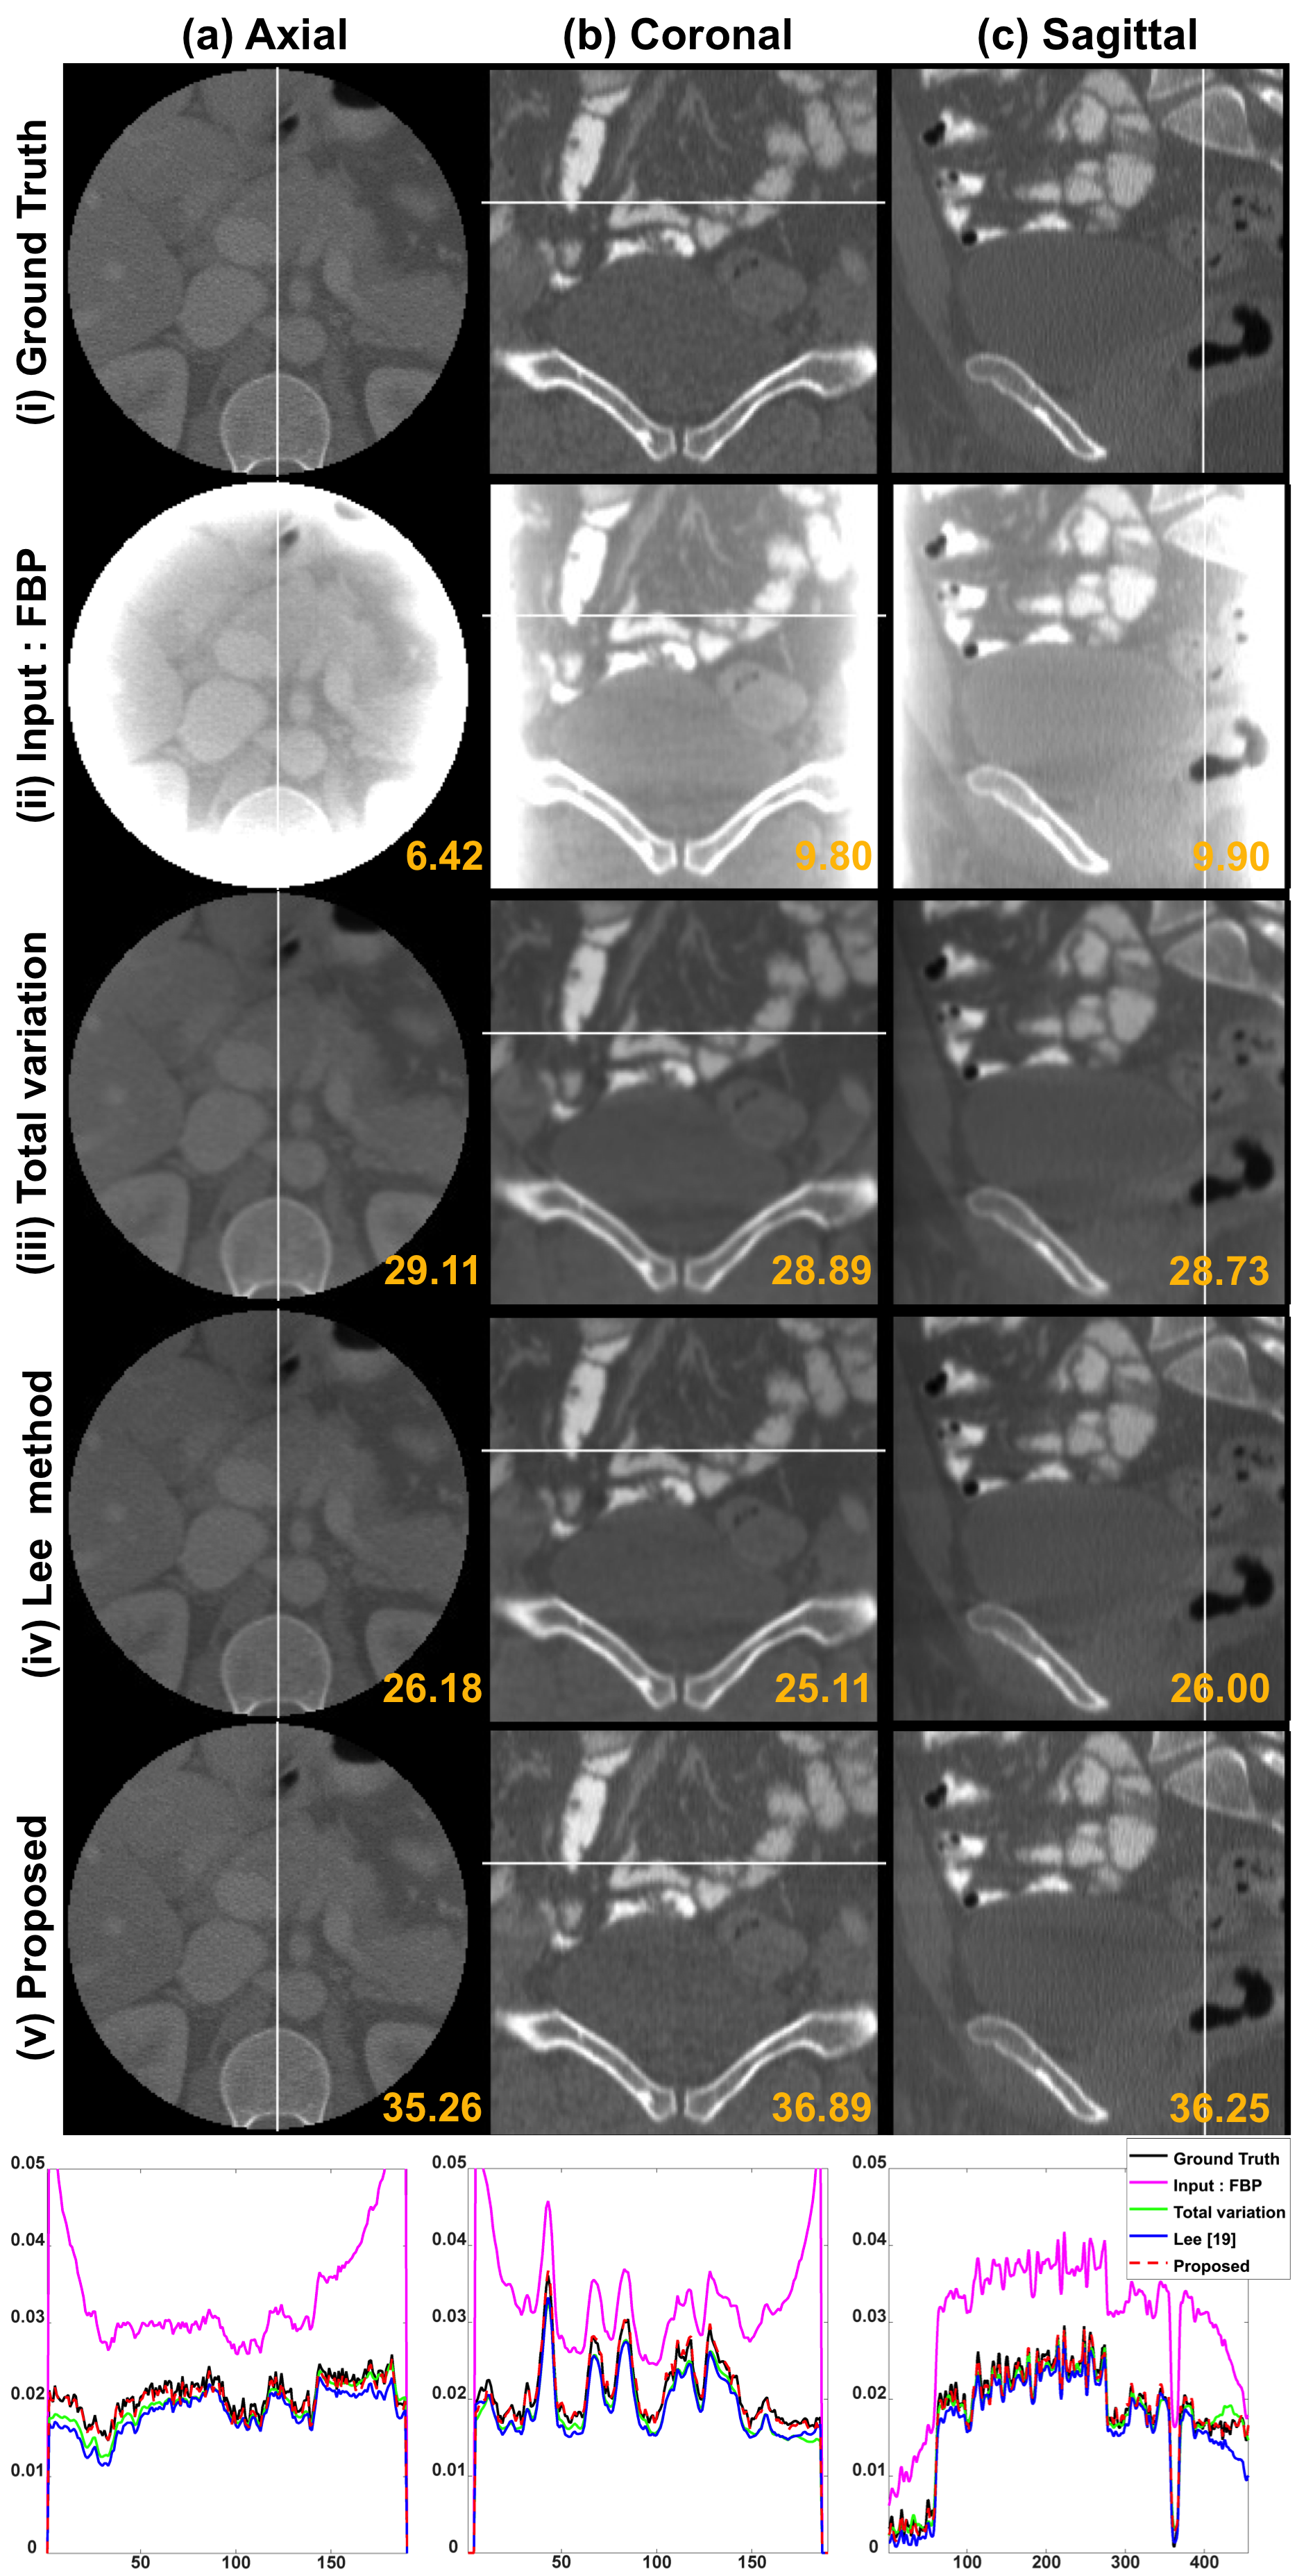

We compared the proposed method with existing iterative methods such as the TV penalized reconstruction [2] and the L-spline based multi-scale regularization method by Lee et al [4]. Fig. 4 shows the ground-truth images and reconstruction results by FBP, TV, Lee method [4] and the proposed method. The graphs in the bottom row in Fig. 4 are the cross-section view along the white lines on the each images. Fig. 5 shows the magnitude of difference images between the ground truth image and reconstruction results of each method. The reconstructed images and the cut-view graphs in Fig. 4 show that the proposed method results have more fine details than the other methods. The error images in Fig. 5 confirm that the high frequency components such as edges and textures are better restored in the proposed method than other method.

We also calculated the average values of the peak signal-to-noise ratio (PSNR) and the normalized mean square error (NMSE) in Table  I. The proposed method achieved the highest value in PSNR and the lowest value in NMSE with about 710similar-to7107\sim 10 dB improvement. The computational times for TV, Lee method [4] and the proposed method were 1.8272s, 0.3438s, and 0.0532s, respectively, for each slice reconstruction. The processing speed of the proposed method is about 34 times faster than the TV method and 6 times faster than Lee method [4].

Figure 4: Reconstruction images by the cone-beam simulation. The last row shows the cut-view plots of the white lines on the images. The number written in the images is the PSNR value in dB.